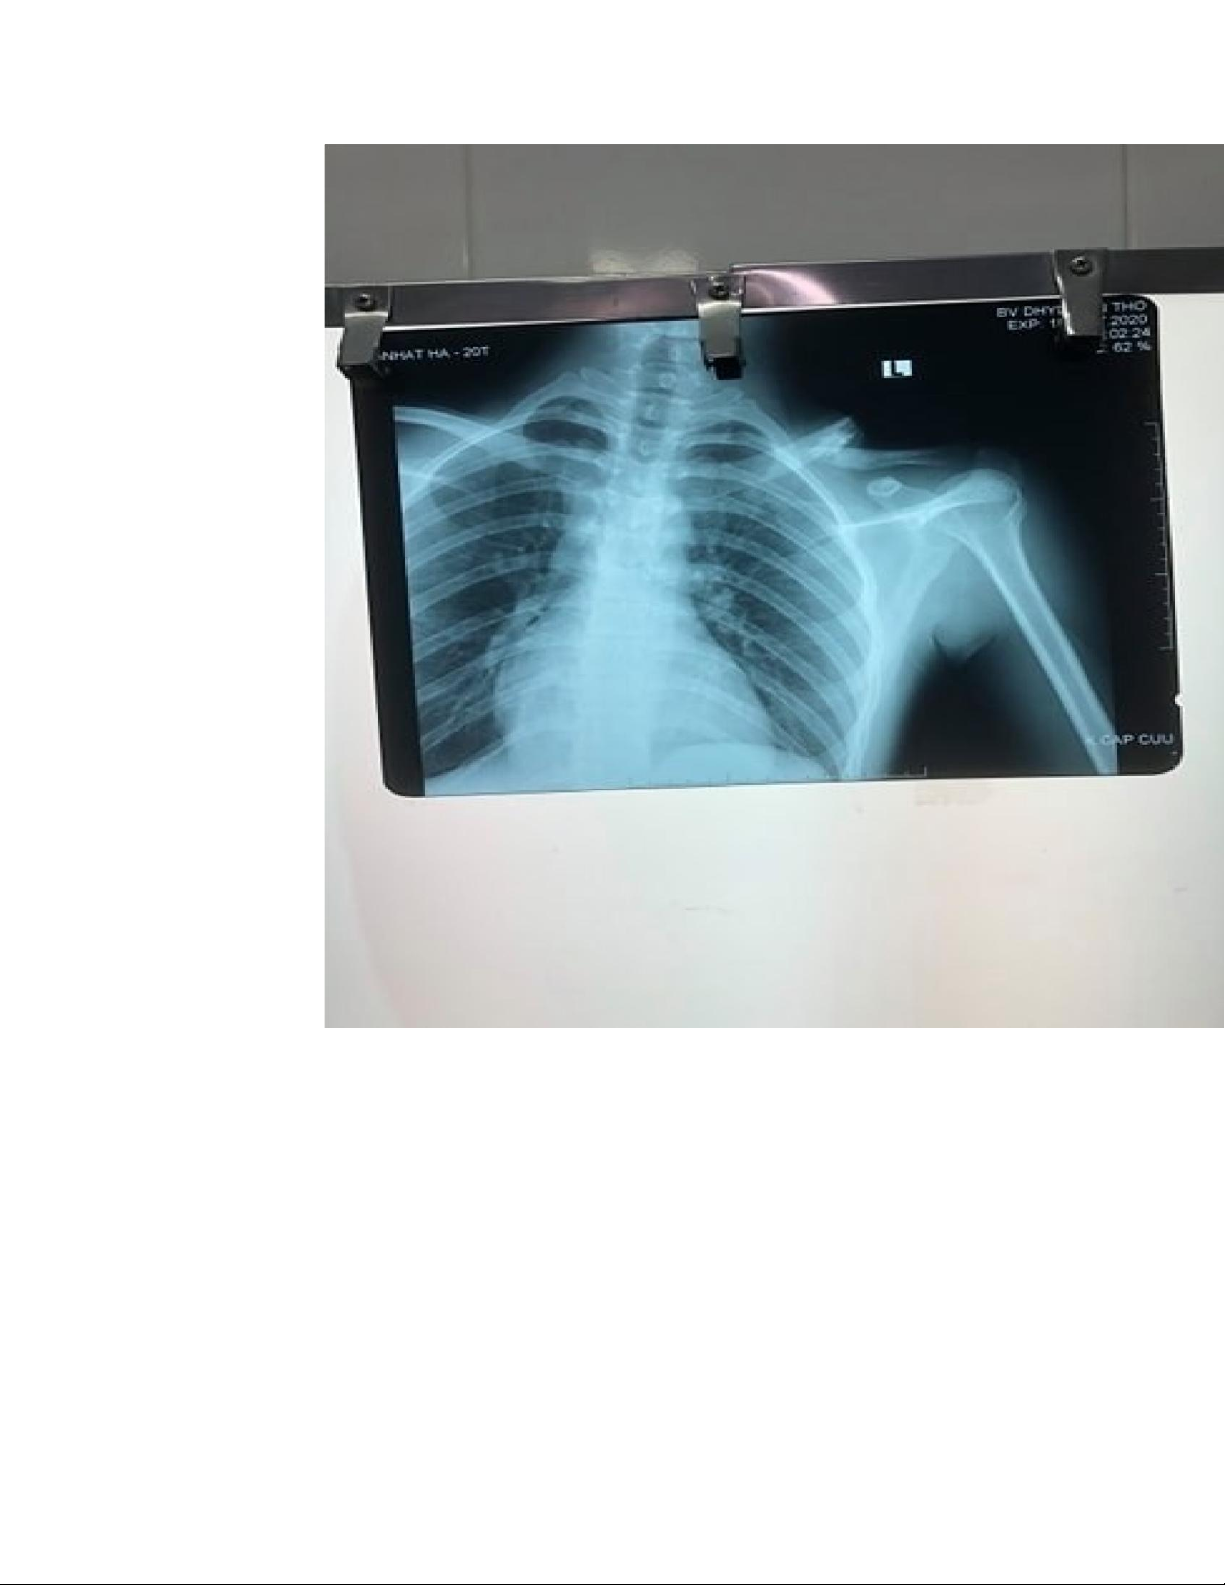

c. Xquang ngực thẳng: Gãy phức tạp 1/3 giữa xương đòn (T), có

mảnh rời, di lệch góc 40o, chồng ngắn 2cm